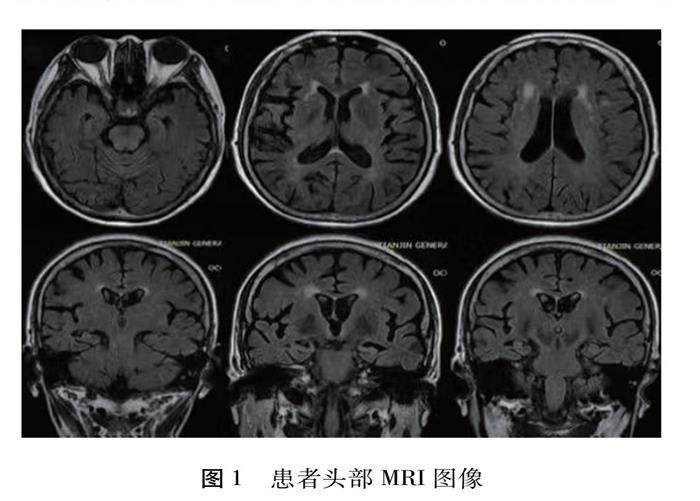

[摘 要] 阿尔茨海默病(AD) 是临床上常见的神经系统退行性疾病,其发病与多种血管危险因素有关。目前临床中对心血管疾病与 AD 之间关系的探讨逐渐增多,两者之间可能通过多种方式产生联系,相互影响。此外,既往也有大手术后 AD 急性进展的报道。本文报道1例有高血压和糖尿病病史的患者,在心肌梗死行经皮冠状动脉介入治疗后出现急性进展的 AD 临床表现,经查符合 AD 诊断标准。(剩余10881字)